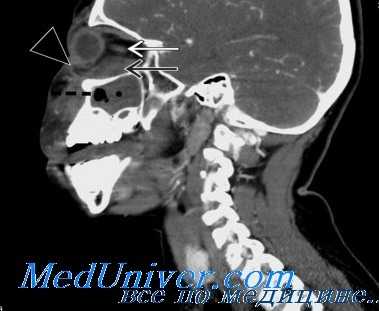

Хирургическое лечение остеомиелита плановое, абсцесса — срочное и начинается по возможности с четкой его локализации. Предположить местонахождение абсцесса можно либо по клиническим симптомам (абсцесс локализуется в зоне, противоположной смещению глаза; его репозиция за счет флюктуации гноя несколько свободнее, чем при целлюлите), либо по данным КТ или МРТ (топография абсцесса, его субпериостальное или орбитальное расположение). От этого зависят место кожного разреза и методика операции. Обязательные условия: все операции выполняют в условиях общей анестезии с использованием микрохирургической техники, разрез тканей проводят послойно.

Субпериостальный абсцесс орбиты

Субпериостальный абсцесс орбиты – гнойное поражение стенки орбиты при воспалении околоносовых пазух. Заболевание характеризуется острым началом, повышением температуры до 39° С, отёком кожи вокруг орбиты, развитием хемоза конъюнктивы, появлением двоения, нарушением движений глазного яблока, резким снижением остроты зрения. Для диагностики применяют визометрию, биомикроскопию, тонометрию, периметрию, рентгенографию орбит и придаточных пазух носа, ультразвуковое исследование глаза и орбиты, КТ или МРТ орбит, придаточных пазух носа и головного мозга. Лечение консервативное (антибиотикотерапия, дезинтоксикационная терапия) и хирургическое (вскрытие, дренирование абсцесса).

Для диагностики применяют стандартные методы: визометрию, биомикроскопию, тонометрию, периметрию. Для точного определения локализации субпериостального абсцесса орбиты дополнительно используют лучевые методики. Рентгенография орбит и придаточных пазух носа в прямой и боковой проекциях позволяет диагностировать куполообразную (экссудативную) отслойку надкостницы орбиты и увеличение денситометрической плотности клетчатки глазницы вокруг очага воспаления.

Ультразвуковое исследование глаза и орбиты выявляет изменение размера ретробульбарного пространства, хода экстраокулярных мышц. КТ или МРТ орбит, придаточных пазух носа и головного мозга помогает определить отслойку периоста в зоне поражения. Кроме того, при субпериостальном абсцессе орбиты требуется консультация отоларинголога, челюстно-лицевого хирурга и нейрохирурга. Проводится бактериальный посев гнойного отделяемого с определением чувствительности к антибактериальным препаратам.